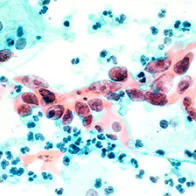

Vaccination to prevent disease is commonplace in Europe today. Certain diseases have already been eradicated by rigorous vaccination campaigns, while others are hoped to be eliminated soon, such as measles and congenital rubella. Yet challenges remain. New vaccines that are being developed against existing diseases such as infections with human papillomavirus and may be developed against newly emerging diseases in the future, need to be monitored and evaluated.

Some vaccines are still underutilised. Although vaccination has become increasingly safe and effective, one of the major challenges we face is opposition in the population against immunisation. We may have become too used to the benefits of vaccination, some diseases now being so rare that we do not even remember how devastating their consequences can be. Immunisation programmes are threatened by insufficient information, by unsubstantiated rumours about adverse effects, or by groups that, for religious or other reasons, are opposed to vaccination. Communication of the correct scientific facts it is therefore important to enable both policy makers and the public to make an informed choice.